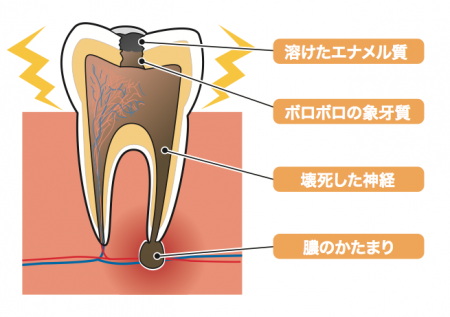

レントゲンには写ってこないことがある為、口腔内では直接チェックして判断します

エナメル質の奥の象牙質まで むし歯が進んだ状態です 甘いものや冷たいものが しみるようになってきます

治療してみると歯の内部で、虫歯が進行しており茶色くなっていました

ここまで進行しても症状がない場合もあります。自覚症状がない為、歯科医院での定期検診を怠り痛みがでてから治療することがほとんどになります。